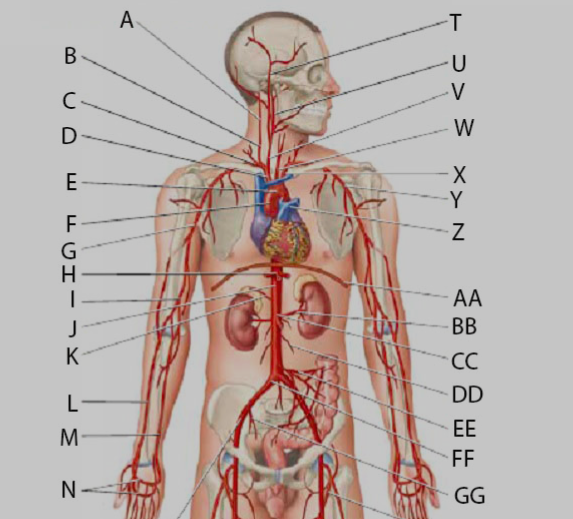

Aortic Arch

Ascending/descending aorta

Basilar artery

Brachiocephalic artery

Brachiocephalic vein

Celiac trunk

Common iliac artery/vein

Femoral artery/vein

Gonadal (=testicular/ovarian) artery/vein

Great saphenous vein

Internal/external/common carotid artery

Internal/external iliac artery/vein

internal/external/common jugular vein

Left/right primary bronchus/bronchi

left/right pulmonary artery/vein

Popliteal artery/vein

Radial artery/vein

Renal artery/vein

Subclavian artery/vein

Superior/inferior mesenteric artery

Superior/inferior vena cava

Thoracic aorta

Abdominal Aorta

Ulnar artery/vein

Ureter

Vertebral artery